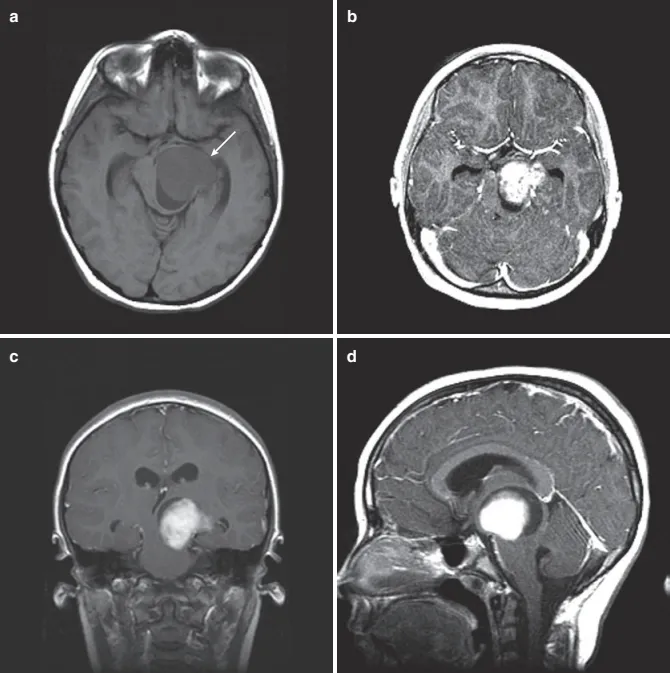

12 岁女孩,进行性右侧肢体无力和共济失调3月。(a) 轴位T1 MRI 显示占位性病变占据脑干左侧被盖区(箭头)。(b)增强后,病灶明显均匀强化。(c) 冠状位T1 MRI增强后显示起源于左侧中脑被盖区的巨大病变,延伸到丘脑。有时,这些病灶被称为“丘脑大脑脚”病变。(d) 矢状位 T1 MRI增强后显示典型的局灶性中脑胶质瘤,中心强化。